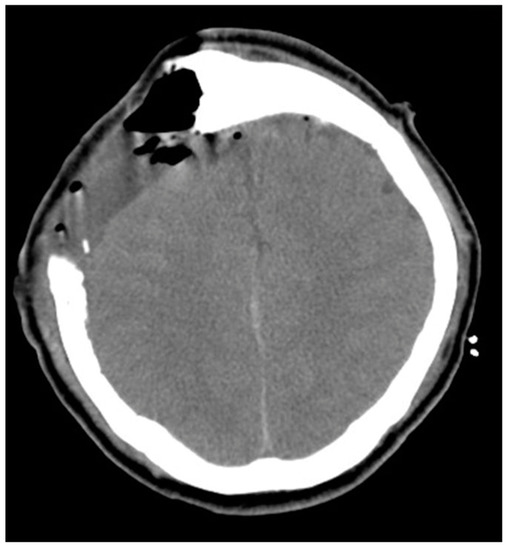

| Tsai et al., 2021 | 55/M | Seizure, loss of consciousness | 91 | bilateral | occluded | II | I | 2/5 left arm and left leg 0/5 right leg | Preserved | Aphasia | Aphasia recovery within 7 days; muscle power recovery within 7 weeks |